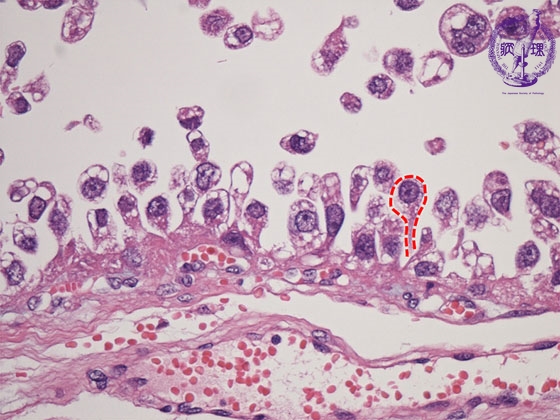

- (8)Clear cell adenocarcinoma of the ovary

Histology (HE stain, high power): Carcioma cells with clear cytoplasm proliferated showing hobnail patterns (nuclei is located at free end of cancer cell as if protruding, red dotted line). The term Hobnail originated from the resembalance between the shape of these cells and the nails with thick head for boot soles.